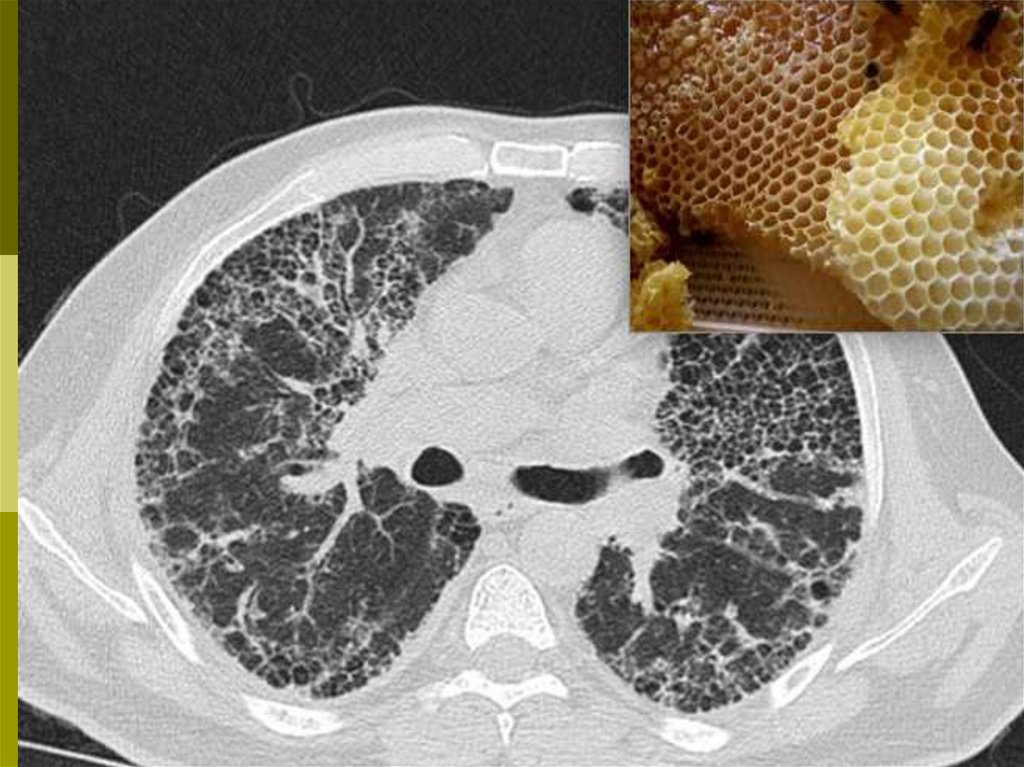

КТВР – снижение прозрачности лёгочной ткани («матовое стекло»)

нижних долей и повышение – верхних долей, сетчато-тяжистый

рисунок, ячеистые просветления («сотовое лёгкое»), сужение

лёгочных полей, высокое стояние диафрагмы

В хронической стадии выявляются признаки

диффузного фиброза – крупная ячеестость

лёгочного рисунка («сотовое лёгкое»)